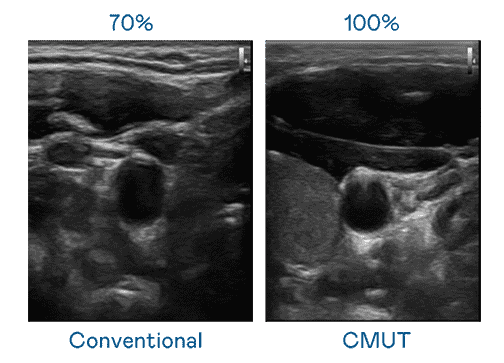

CMUT 技术是一种用电容式微机电元件来产生超音波讯号的技术。。与传统 PZT 压电式技术相比,,,,CMUT 频宽增加 30%,,,,更宽频的超音波讯号让影像解析度大幅提升,,,,是实现高影像品质医疗超音波扫描、、、促进精准医疗发展的关键技术。。。

大频宽带来超清晰影像

超音波影像的解析度高低,,,首先取决于探头能发出的讯号频宽。。。。2468BET CMUT 可提供高清晰的超音波讯号,,,提供高频宽、、、高灵敏度、、、、影像纹理细节更高的超音波影像,,协助医护人员缩短影像判读时间及利用精准的医疗影像进行诊断。。。。